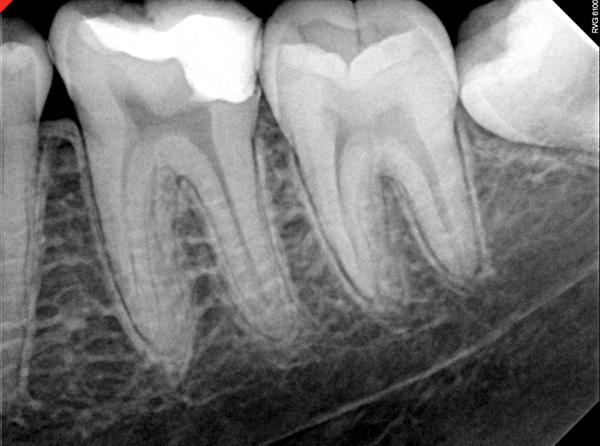

Fig 11. Preoperative radiograph. Courtesy of Dr. Guillaume Jouanny.

Figure 11

Fig 12. Postoperative radiography after full pulpotomy was performed. Courtesy of Dr. Guillaume Jouanny.

Figure 12

Fig 13. Tooth was asymptomatic at 1-year follow-up. Courtesy of Dr. Guillaume Jouanny.

Figure 13

Fig 14. Contralateral tooth at 1-year follow-up. Courtesy of Dr. Guillaume Jouanny.

Figure 14